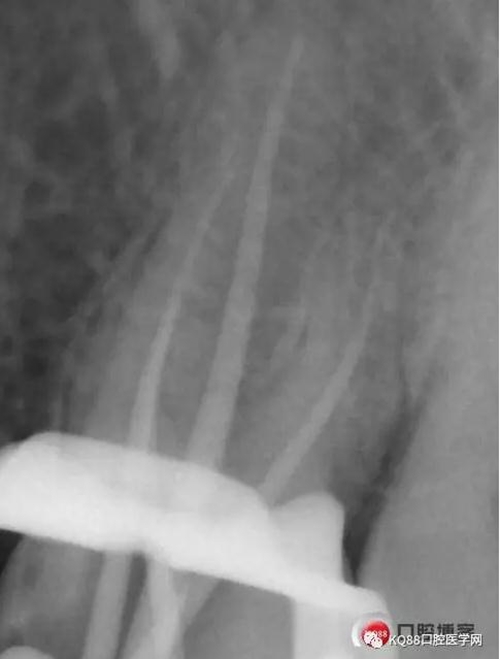

當(dāng)我第一次完成操作后,再次拍了一個(gè)插針片,發(fā)現(xiàn),距離根尖孔有1.5mm,書上說(shuō)的是2mm安全區(qū),可能如果隨意點(diǎn),就直接充填了,我想說(shuō)明的是,我們做根管,千萬(wàn)不要馬虎,不要湊合,一定嚴(yán)謹(jǐn)?shù)膽B(tài)度,于是我重新再回到C銼,再開(kāi)始耐心的預(yù)備,完成之后,再拍攝了插針片。

此次明顯可以看見(jiàn)根尖分開(kāi)了兩個(gè)根尖孔,根管治療永遠(yuǎn)就只是那一點(diǎn),如果都只是隨便做一下,我相信,沒(méi)有復(fù)雜的牙齒,根管治療都會(huì)很簡(jiǎn)單,態(tài)度決定一切,我不敢說(shuō)我做的會(huì)很好,但是我會(huì)靜下心來(lái),慢慢操作,這樣才能做得對(duì)的起自己和患者。于是根充完成,再次拍攝。